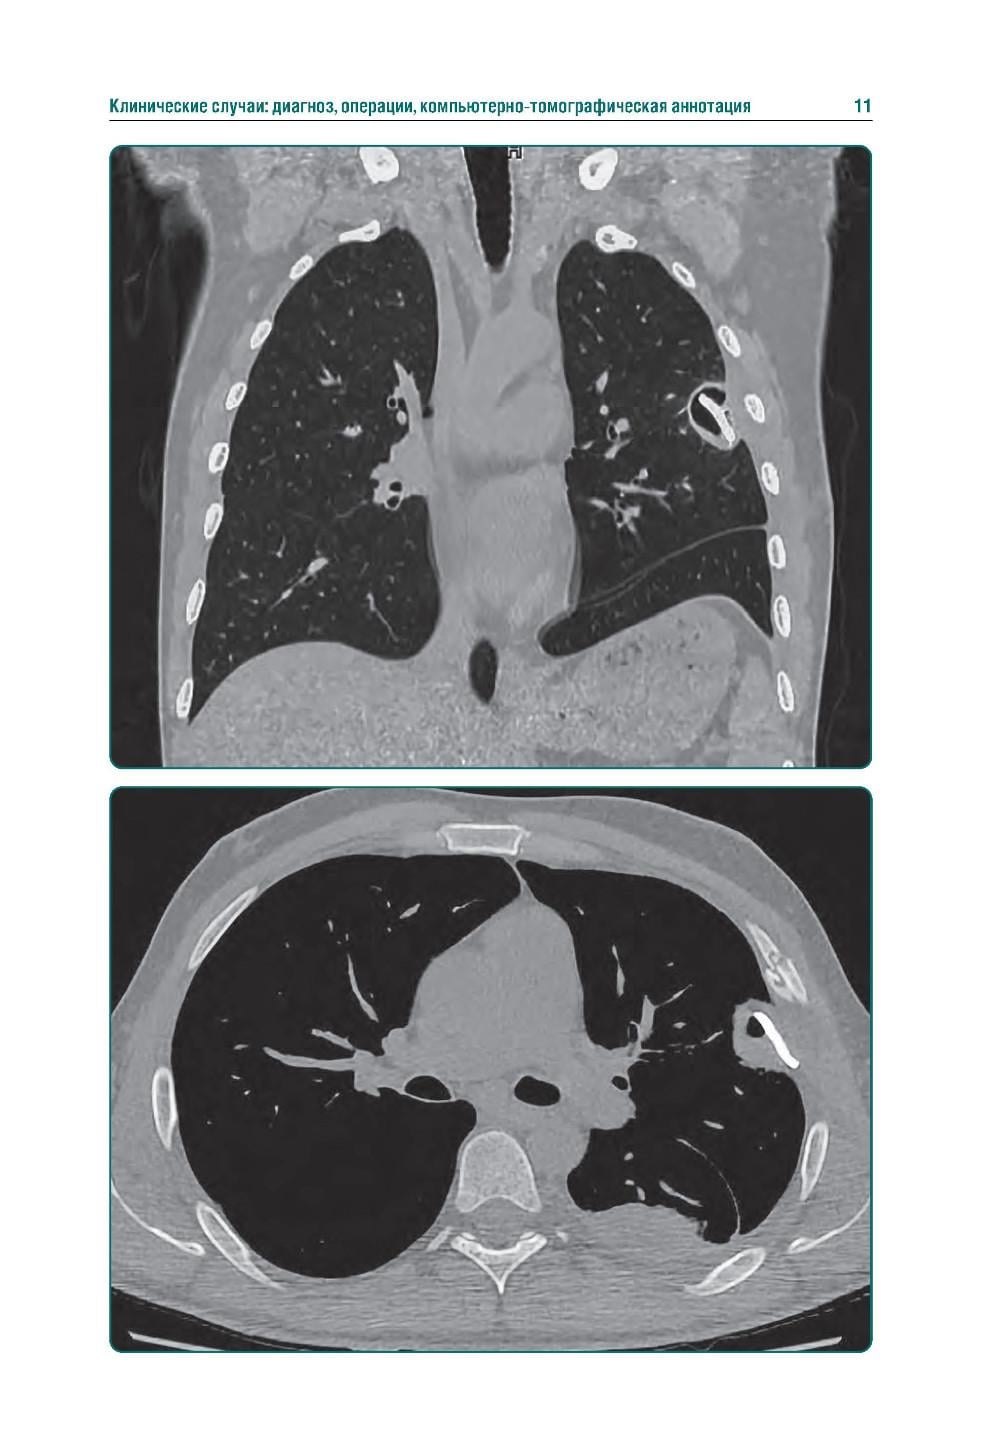

Аннотация: КТ-признаки поражения легких и грудной клетки при боевой травме: атлас

Издание представляет собой первый в Российской Федерации атлас, иллюстрирующий различные виды поражения легких, плевры и других структур грудной клетки у пациентов с боевыми ранениями. В современных условиях количество таких пациентов увеличивается, поэтому существенно возрастает значимость различных видов боевых травм, в том числе повреждений грудной клетки. В атласе представлены уникальные КТ-изображения различных видов боевой травмы грудной клетки, полученных в условиях современных вооруженных конфликтов. Помимо описания характера, условий получения травмы и выявленных повреждений, есть возможность просмотра изображений в формате DICOM. Атлас предназначен для врачей-рентгенологов, торакальных хирургов, пульмонологов, а также врачей других специальностей, занимающихся диагностикой и лечением пациентов с боевыми травмами.| Издательство | ГЭОТАР-Медиа |